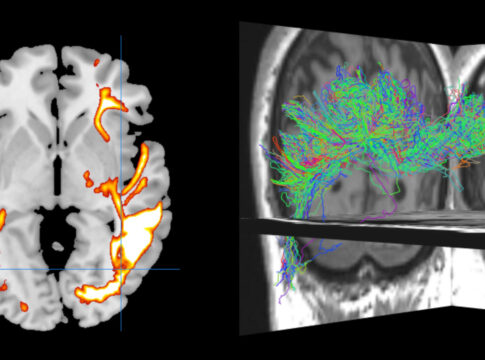

Abstract Very preterm birth (VPT; <32 weeks’ gestation) leads to a situation where crucial steps of brain development occur in an abnormal ex utero environment, translating to vulnerable cortical and subcortical development. Associated with this atypical brain development, children and adolescents born VPT are at a high risk of socio-emotional difficulties. In the current study, we unravel developmental changes in cortical gray matter (GM) concentration in VPT and term-born controls aged 6–14 years, together with their associations with socio-emotional abilities. T1-weighted images were used to estimate signal intensities of brain tissue types in a single voxel (GM, white matter, and cortico-spinal fluid) and extract GM concentration disentangled from the presence of partial volume effects (PVEs). General linear model analysis was used to compare groups. Socio-emotional abilities were assessed and associations with GM concentration were explored using univariate and multivariate analyses. The effects of prematurity were far-reaching, with intricated patterns of increases and decreases of GM concentration mainly in frontal, temporal, parietal, and cingular regions. Better socio-emotional abilities were associated with increased GM concentration in regions known to be involved in such process for both groups. Our findings suggest that the trajectory of brain development following VPT birth may be fundamentally distinctive and impact socio-emotional abilities.

Cortical alterations after very preterm birth and the association with socio-emotional abilities from childhood to early adolescence